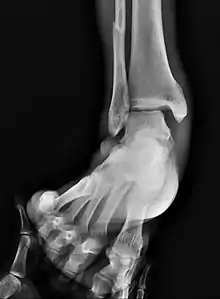

Fracture of both sides of the ankle with dislocation as seen on anteroposterior X-ray. (1) fibula, (2) tibia, (arrow) medial malleolus, (arrowhead) lateral malleolus

On X-rays, there can be a fracture of the medial malleolus, the lateral malleolus, and/or of the anterior/posterior margin of the distal tibia. The posterior margin (known as the posterior malleolus) is much more frequently injured than the anterior aspect of the distal tibia. If both the lateral and medial malleoli are broken, this is called a bimalleolar fracture (some of them are called Pott's fractures). If the posterior malleolus is also fractured, this is called a trimalleolar fracture.